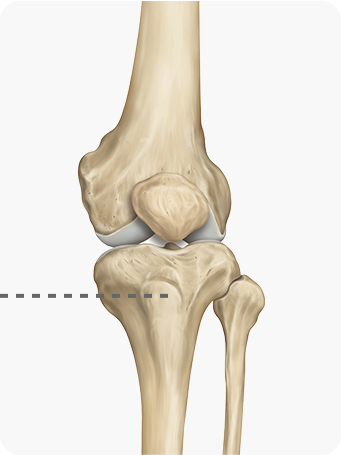

경골을 절골하여 원하는 각도로 벌려 무게 중심이

바깥쪽으로 옮겨지도록 교정

합니다. 절골한 부위를

금속판과 나사로 고정해 뼈가 안정적으로 붙도록 합니다.